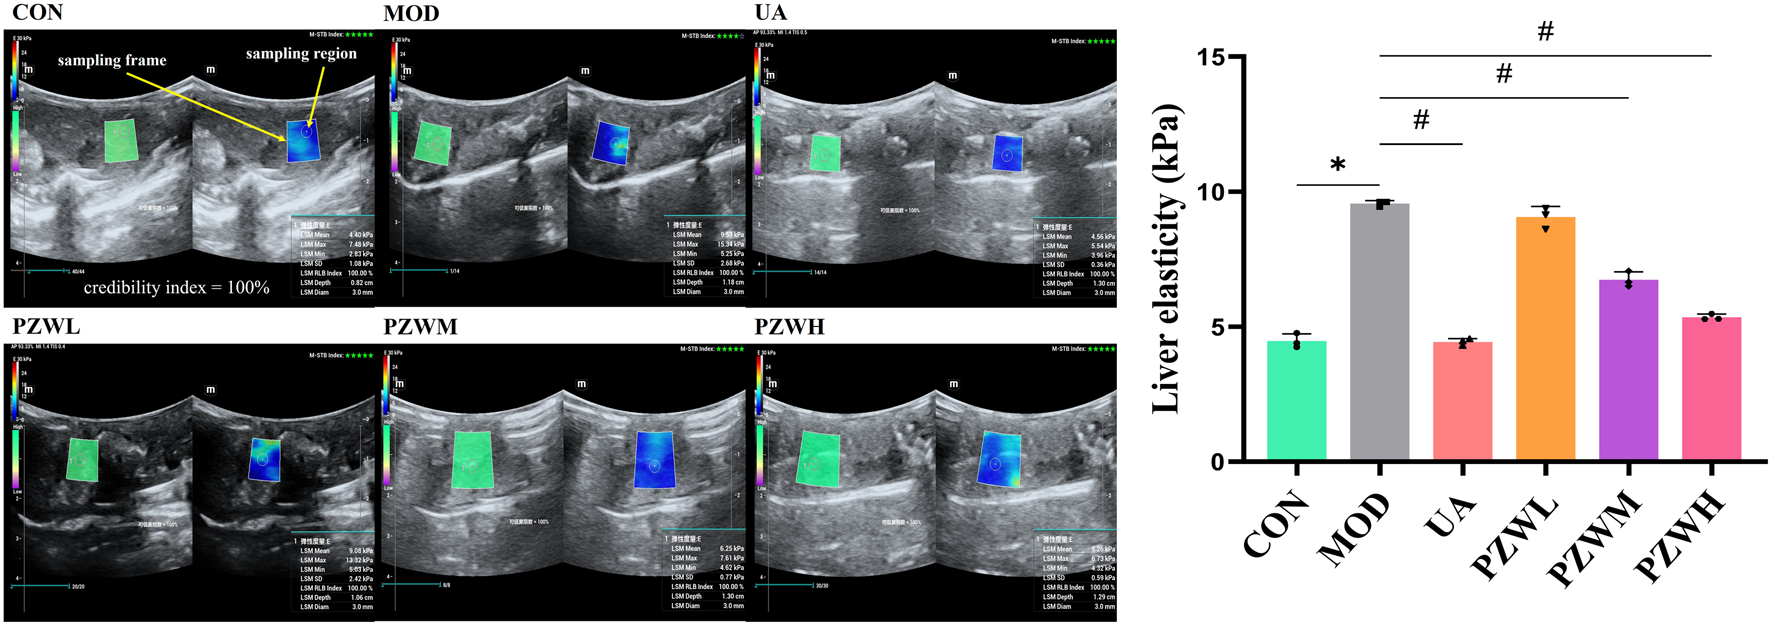

3.2 Liver stiffness

Unlike CON, the MOD group was characterized by a higher level of liver stiffness as indicated by the shear wave elastography measurement (Figure 1). They had reduced food intake (from 1,668.8 ± 12.7 g/group to 422.3 ± 15.3 g/group) and body weight (from 199.9 ± 1.2 g/rat to 146.8 ± 0.7 g/rat). They were physically less active with yellowish dull fur and had increased respiration rate (from 88.38 ± 2.37 breath/min to 134.50 ± 1.01 breath/min) and heart rate (from 435.20 ± 1.97 beat/min to 501.78 ± 3.75 beat/min). Treatment of these rats with PZW generally reduced their liver stiffness in the following dose progression: PZWH < PZWM < PZWL (Figure 1; p < 0.05), increased their food intake (1,427.9 ± 313.2 g/group), body weight (297.0 ± 54.2 g/rat) and physical activity, and reduced their respiration rate (94.50 ± 10.53 breath/min), heart rate (417.04 ± 11.06 beat/min) as well as fur dullness. Rats treated with PZWH had a liver elasticity similar to those of receiving the ursodeoxycholic acid (Figure 1).

FIGURE 1

The liver ultrasonogram and elasticity profiles of normal rats, rats with carbon tetrachloride-induced liver fibrosis and those treated with UA and PZW. The elasticity value was expressed as mean ± standard deviation. * p < 0.05 against CON, # p < 0.05 against MOD.